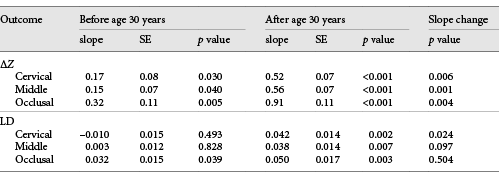

3-Dimensional X-Ray Micro-CT

Fig. 1

Micro-CT images. a Sample with young dental age. b Sample with advanced dental age. c Sample with wear facet (red star). Coronal sections show only the decayed area of the samples. Sagittal sections: gray lines signal areas exposed to demineralization. The green line signals the central area of the block that has been protected (internal control). Left side shows the wear facet.

ΔZ and LD analyses were performed using ImageJ software v1.8.0_66 by a previously trained examiner, who was blinded to the estimated dental age. ΔZ consisted of the difference in the mineral concentration profiles of the internal control and experimental enamel, up to a depth of 200 µm from the surface. The internal control and experimental profiles were 150 µm apart from each other. The quantification of the mineral concentration was performed from an equation described previously [Wong et al., 2004], using an enamel mineral empirical formula with a density of 2.99 g/cm3 [Elliott, 1997]. Based on the X-ray emission peak energy of 59 keV, the mass attenuation coefficient for enamel mineral was 0.406434 cm2/g, and the linear attenuation coefficient for aluminum was 0.767326/cm. Areas with mineral concentration <2.63 g/cm3 (corresponding to a mineral volume of 88%) in the control area and enamel blocks with <3 areas for analysis were excluded.

Enamel locations with wear facets showed significantly higher ΔZ and LD than the locations without facets (Fig. 1c). Of the 261 samples, estimated tooth age ranged from 10.9 to 93.4 years. Of the 6 areas analyzed in each specimen, 12.7% of them had wear facets, which were more frequent in the occlusal third of the specimens. Based on linear regression, the ΔZ value for the youngest (10.9 years old) was 10.57 µm/g/cm3 and for the oldest (93.5 years old) it was 197.92 µm/g/cm3.

This study contributes to the limited literature on the effect of enamel age on caries susceptibility. Although conceptually ideal, designing a clinical study for this purpose would be challenging, due to the difficulty in obtaining enough dental samples of different ages for the specific laboratory analytical testing, within a reasonable amount of time. To overcome this limitation, we used already extracted and deidentified human premolars. The ages of the teeth were estimated by validated forensic methods, similar to the approach used in our previous study [Algarni et al., 2018]. The controlled conditions of this in vitro study allowed us to observe a significant decrease in the integrated mineral concentration loss and increase in the depth of the caries-like lesions, as functions of a tooth aging (Fig. 1a, b). This contrasts with the previous findings that indicated reduction in the artificial caries susceptibility in older enamel [Kotsanos and Darling, 1991]. Structural, chemical, and physical factors related to enamel can help clarify such differences.